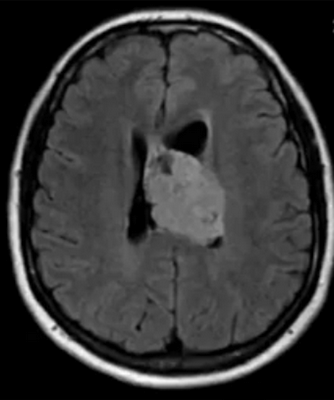

Глиобластома на МРТ головного мозга без контраста

- глиобластомы — злокачественные опухоли, которые отличаются высокой скоростью роста и склонностью к инвазии. Выглядят на снимках, как образования неправильной формы, с нечеткими фестончатыми контурами и выраженным перифокальным отеком. Дают выраженный масс-эффект, смещают головной мозг в полости черепа, повреждая его на отдалении от своего местоположения;